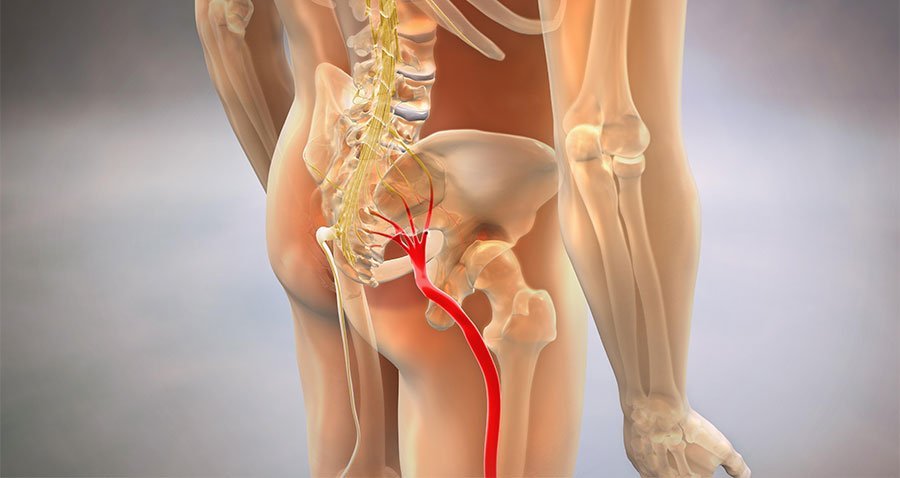

Sciatica. Diabetic neuropathy. Peripheral nerve damage. Post-chemotherapy nerve injury. Different diagnoses — different names, different origins, different doctors.

But the same inflammatory marker shows up in 89% of chronic cases — regardless of the diagnosis: a protein called PI-16 that keeps the nerve pain signal running even after the original injury has healed, even after treatment, even after years.

The label on your diagnosis is different. The mechanism underneath is the same. That's why a formula built to neutralize PI-16 works across all of these conditions — and why most supplements fail across all of them. They were built for the symptom. Not the signal.

Whether you're dealing with sciatic nerve compression, peripheral neuropathy, diabetic nerve damage, or post-chemotherapy nerve injury — persistent nerve discomfort tends to involve three overlapping biological mechanisms:

Neuroinflammation

Inflammatory proteins (like PI-16) attack nerve tissue directly — causing burning, shooting, and electric shock sensations throughout the body

Oxidative Nerve Stress

Free radical damage impairs nerve signal transmission — leading to numbness, tingling, cold extremities, and loss of feeling

Impaired Neural Repair

Slow or blocked nerve regeneration keeps damage accumulating — making symptoms progressively worse without targeted support

We refer to this pattern as the Inflammatory Nerve Triad.

This framework applies whether your nerve pain is rooted in sciatica, type 2 diabetes, peripheral neuropathy, post-surgical damage, or chemotherapy. The pathways are the same. The required support is the same.